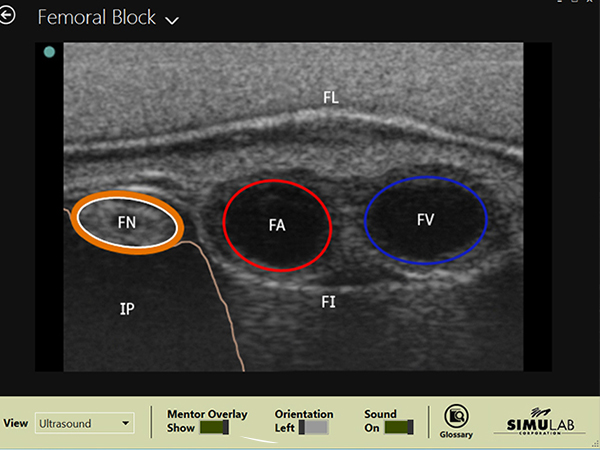

Ultrasound Anatomy:

• Femoral nerve.

• Femoral artery (pulsatile) and vein (pressurized).

• Fascia lata and iliacus Iliopsoas.

• Inguinal ligament.